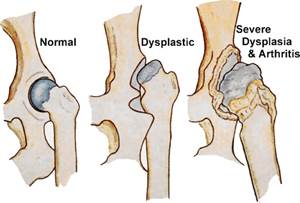

Тазобедренный сустав – простой, многоосный. Состоит из бедренной кости и вертлужной впадины, которую, в свою очередь, образуют три тазовые кости, дополнительно сустав фиксируется круглой связкой. На тазобедренный сустав приходится основной вес как при движении животного, так и в состоянии покоя, что относит к группе риска все крупные и гигантские породы.

Дисплазия определяется рядом разнообразных нарушений в развитии:

- неконгруэнтность суставных поверхностей;

- недоразвитая (чаще всего уплощенная) вертлужная впадина;